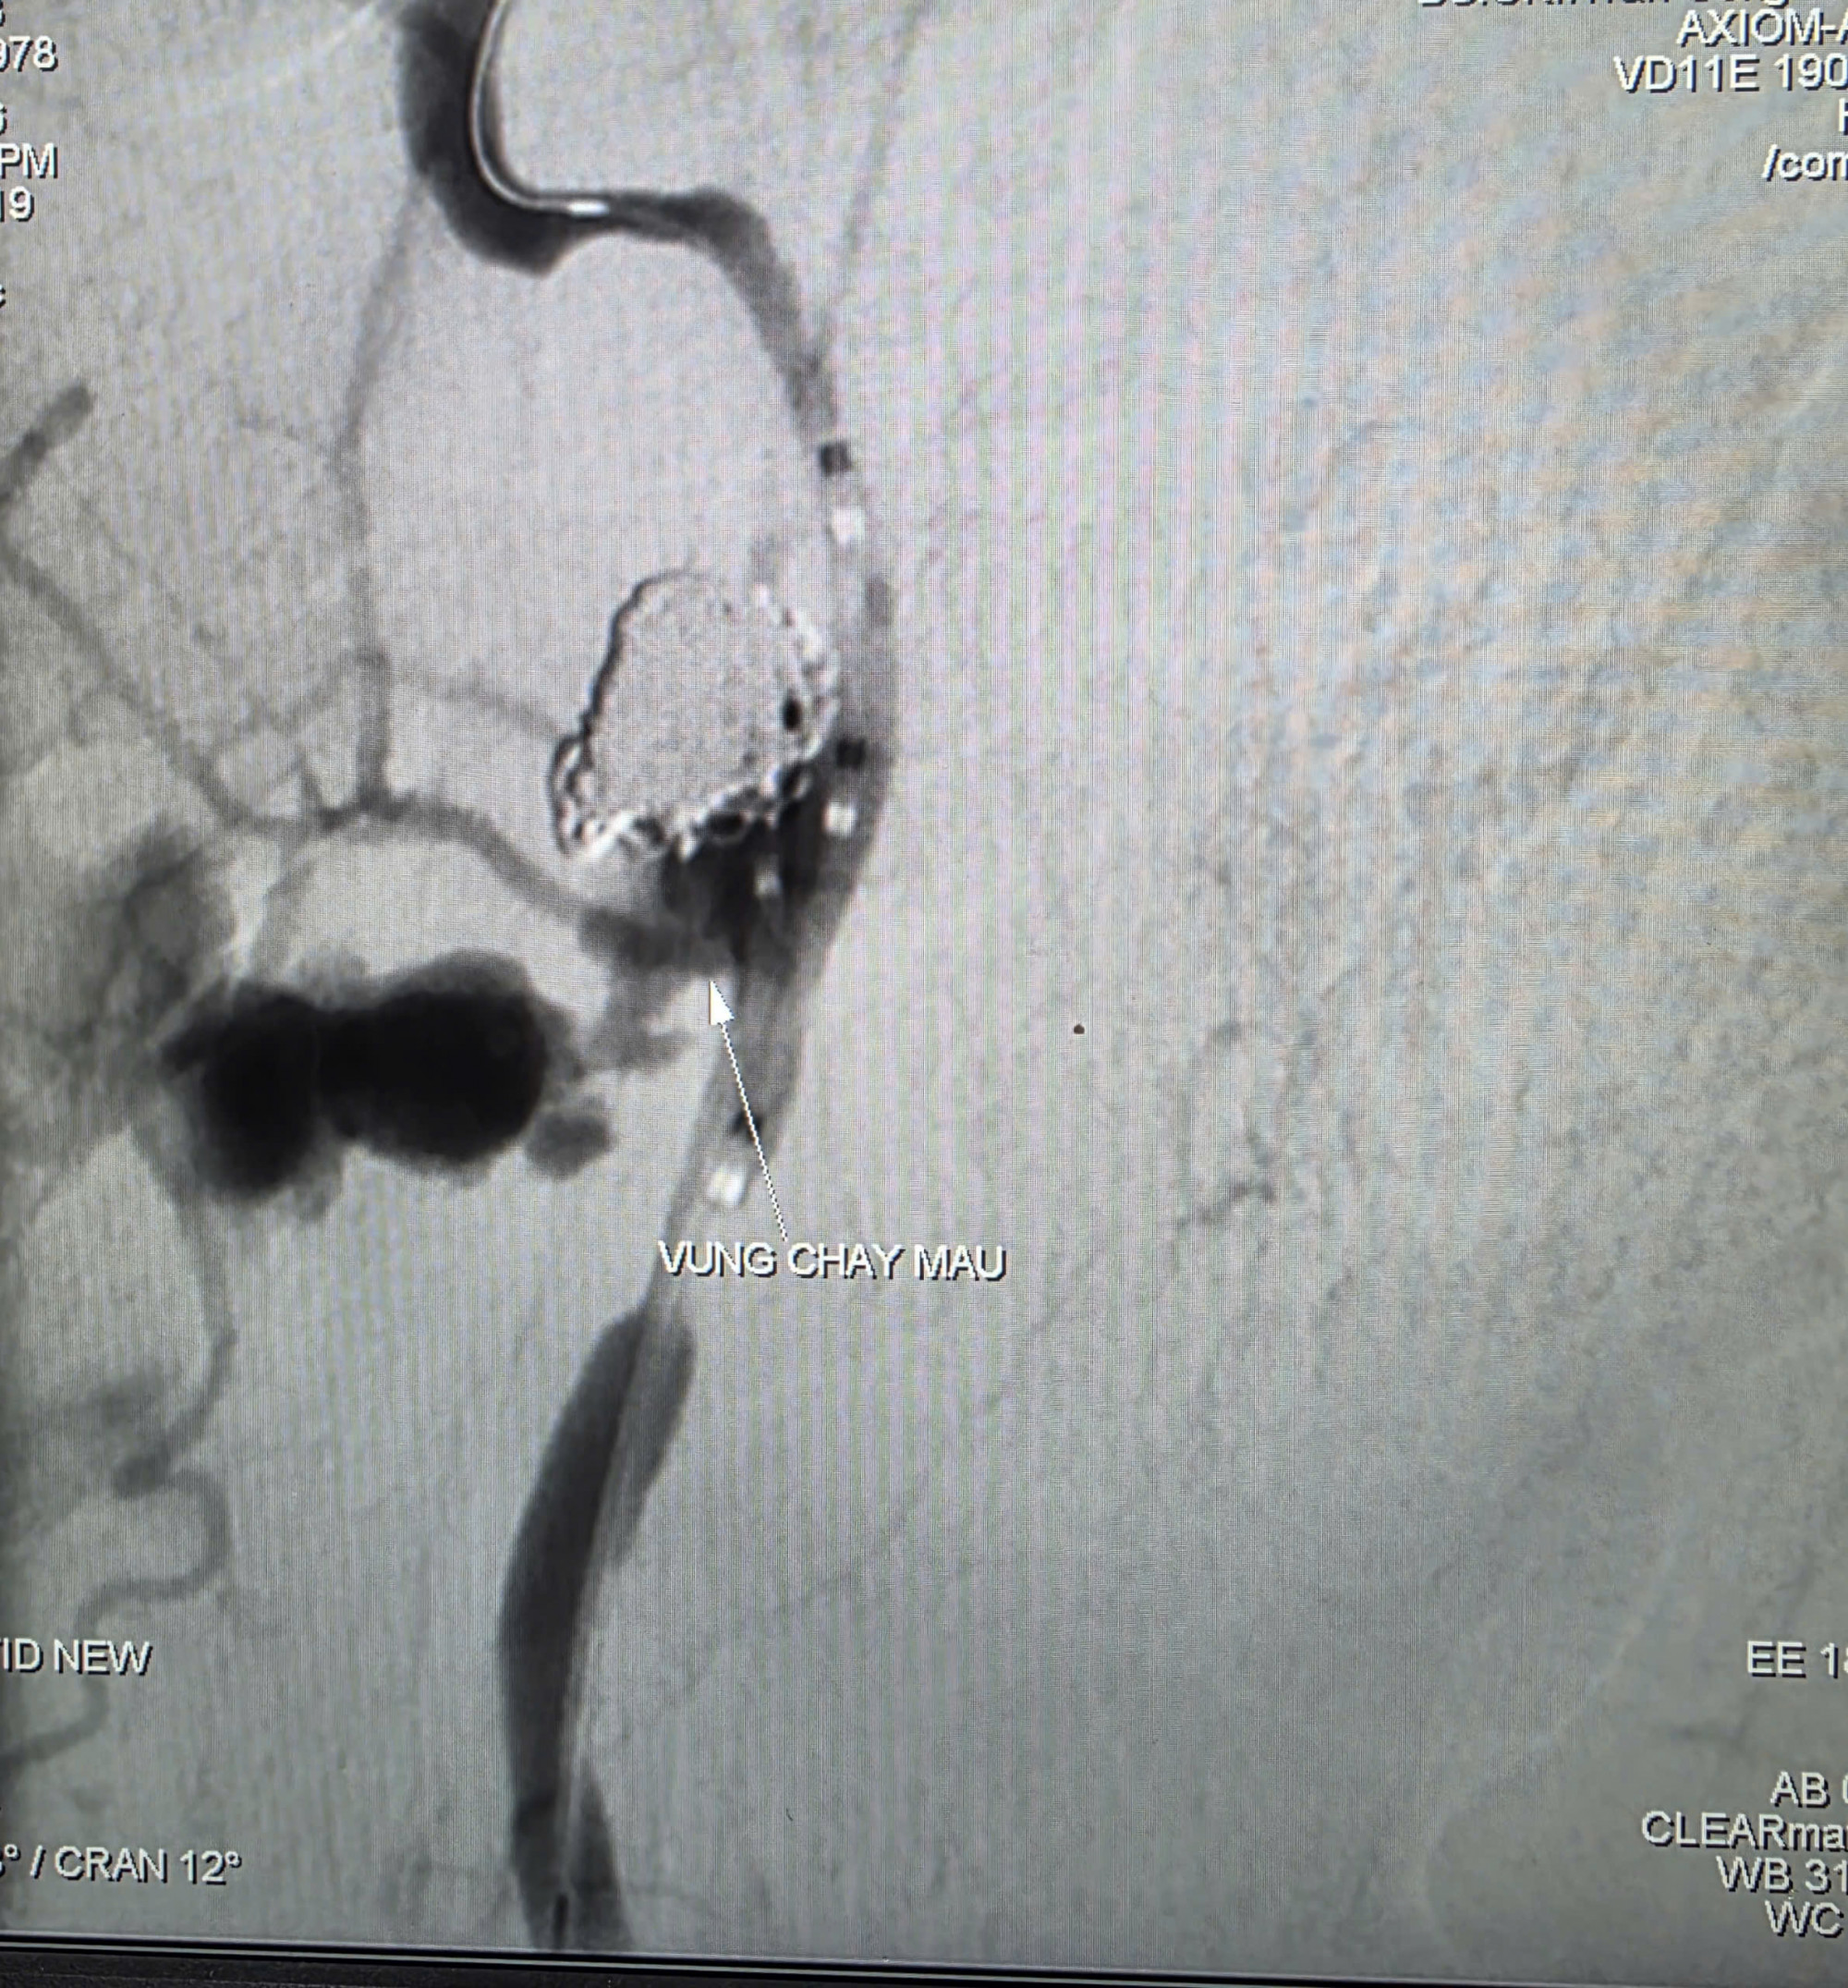

Trước tình huống nguy kịch, nguy cơ mất máu ồ ạt, các bác sĩ quyết định thực hiện chụp và can thiệp cầm máu dưới mạch số hóa xóa nền. Kết quả ghi nhận ổ giả phình động mạch cảnh trong phải đoạn cổ, dưới nền sọ, kích thước 4,2 x 4,8 mm, cổ túi phình rộng và đang chảy máu.

Các bác sĩ đã dùng bóng chẹn dòng chảy kiểm soát lượng máu chảy ra từ túi phình và tiếp tục luồn vi ống thông chọn lọc đến vị trí túi phình và tiến hành thả 9 vòng xoắn kim loại để gây tắc hoàn toàn ổ giả phình và động mạch cảnh trong phải, nhằm kiểm soát triệt để nguồn chảy máu.

Chụp kiểm tra từ động mạch cảnh trong trái cho thấy có tuần hoàn bàng hệ nuôi bán cầu não phải qua động mạch thông trước, đảm bảo tưới máu não sau can thiệp. Thời gian hoàn tất can thiệp là 90 phút.